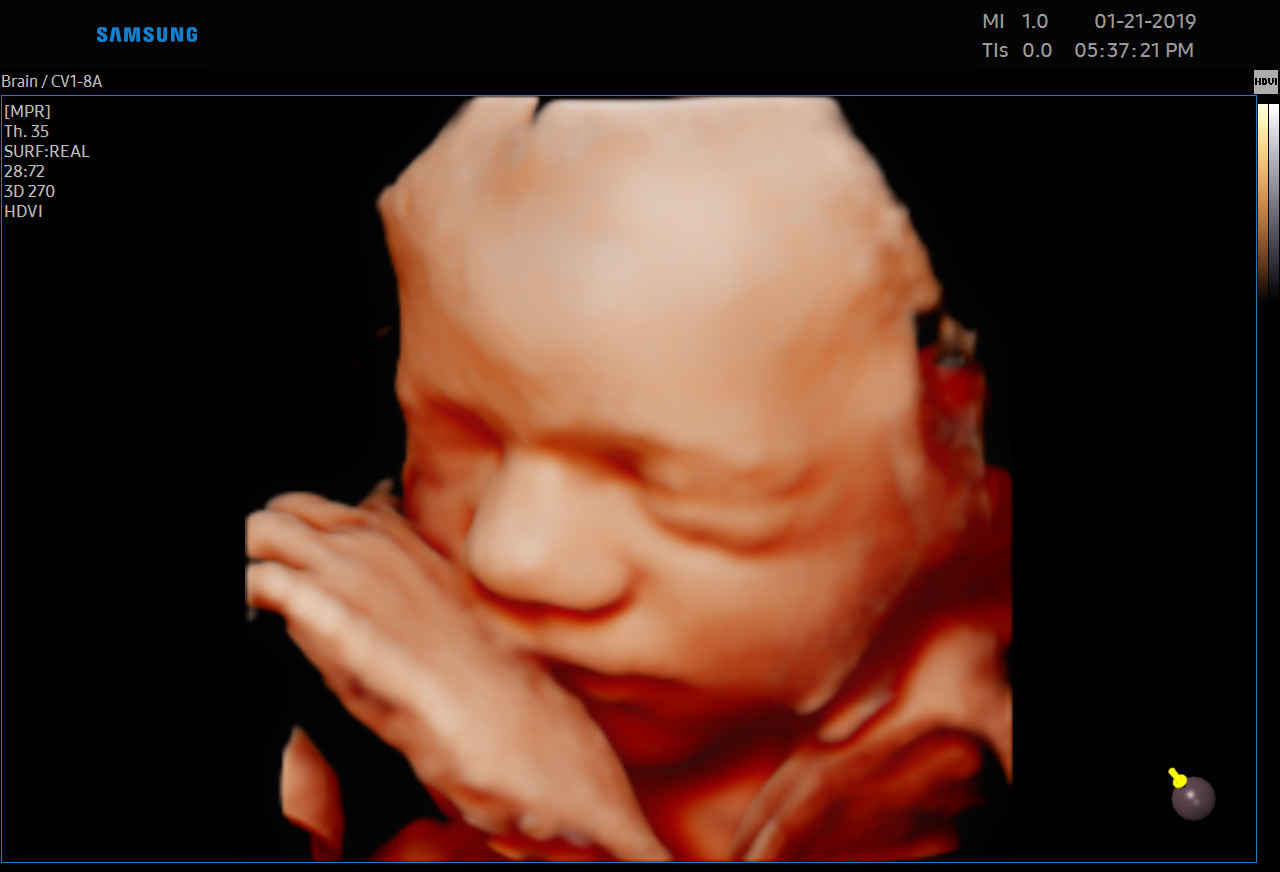

Każdą kobietę w ciąży otaczamy kompleksową opieką, czuwając nad jej zdrowiem oraz prawidłowym rozwojem płodu. Podczas regularnych wizyt, zlecamy odpowiednie badania laboratoryjne. Korzystając z najnowszej generacji aparatu USG, przeprowadzamy bardzo dokładną diagnostykę obrazową – łącznie z USG 3D/4D płodu.